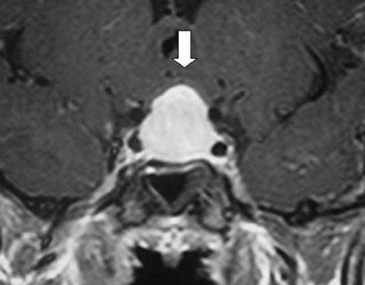

A los 17 años de edad la madre consulta por notar compromiso del estado general, decaimiento, cefalea y polidipsia importante (>4 L/d). Dentro del estudio la RNM cerebral mostró un proceso expansivo mayor a 2 cm, que comprimía el quiasma óptico, sin invasión de los senos cavernosos. Esta imagen se catalogó como macroadenoma hipofisiario intra y supraselar (Figura 1 y Figura 2). En estudio, la imagen T1 sagital sin gadolinio, mostró una silla turca de tamaño normal con un significativo aumento de volumen de la hipófisis, la cual mostró intensidad de señal normal y homogénea. El tallo hipofisiario estaba ascendido y no se reconocía claramente la señal espontánea hiperintensa de la neurohipófisis. En el corte coronal con gadolinio se evidenció claramente la glándula aumentada de tamaño, protruyendo hacia cefálico, con ocupación de la cisterna supraselar y rechazando el quiasma óptico. La impregnación del contraste es difusa y homogénea, sin defectos de captación glandulares que sugieran lesiones focales de tipo adenomatoso o de degeneración quística.